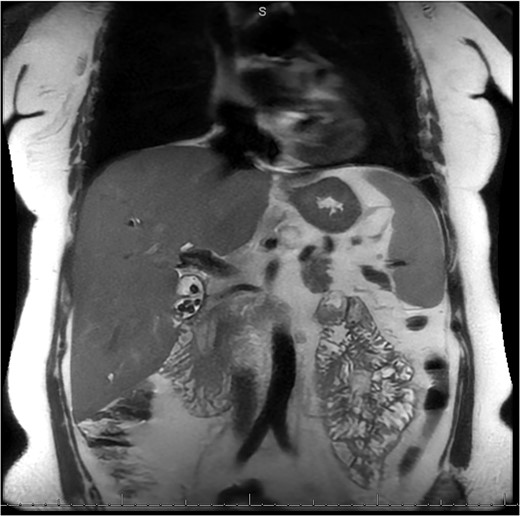

A 49-year-old female with a history of ADPKD and multiple liver cysts, 13-months status post subtotal cholecystectomy, endoscopic retrograde cholangiopancreatography with biliary sphincterotomy and balloon stone extraction, presented to the emergency department with fever and a 4-day history of discomfort in the right upper quadrant. At the time of the initial cholecystectomy, total cholecystectomy could not be performed due to extensive adhesions, and subtotal cholecystectomy with complete evacuation of the stones was done instead. Magnetic resonance cholangiopancreatography (MRCP) done at that time showed a dilated common bile duct (CBD) to 1.5 cm, intra and extrahepatic biliary dilatation, multiple liver cysts measuring up to 2 cm, and multiple stones in the CBD, including at the level of the ampulla (Fig. 1). Computerized tomography scan at the time of the second admission showed acute cholecystitis and she had mildly elevated transaminases, but there was no evidence of cholestasis or pancreatitis. MRCP showed minor proximal intrahepatic biliary dilation and cholelithiasis but no duct calculi (Figs 2–4). A laparoscopic cholecystectomy was attempted with extensive adhesiolysis between the gallbladder and surrounding omentum and mesocolon, but the cystic duct could not be isolated, and ultimately the cased was converted to open. While removing the gallbladder in a top-down fashion, a small bile leak was identified right at the closed end of the gallbladder remnant, where the bile duct was adhered to the gallbladder wall. Intraoperative cholangiogram was obtained through a small perforation in a right posterior bile duct at the site of attachment, which showed right posterior, right anterior and left hepatic ducts of equal size converged at a trifurcation (Fig. 5). The duct was repaired over a T-tube and observed throughout the rest of the case and no bile leak was identified. The gallbladder was opened along its lateral edge, revealing a hugely dilated cystic duct with ~10 to 12 marble-sized stones packed within the gallbladder remnant and cystic duct down to the juncture with the common bile duct. All the stones were removed and the safe portion of the gallbladder remnant was resected leaving the side attached to the bile duct in situ due to the Mirizzi anatomical variant. The cystic duct was oversewn along with the remnant of the gallbladder wall. Pathology showed acute-on-chronic cholecystitis with cholelithiasis. Repeat MRCP showed no retained stones in the biliary tree. The recovery course was unremarkable.

MRI/MRCP from second hospitalization demonstrating liver and kidney cysts.